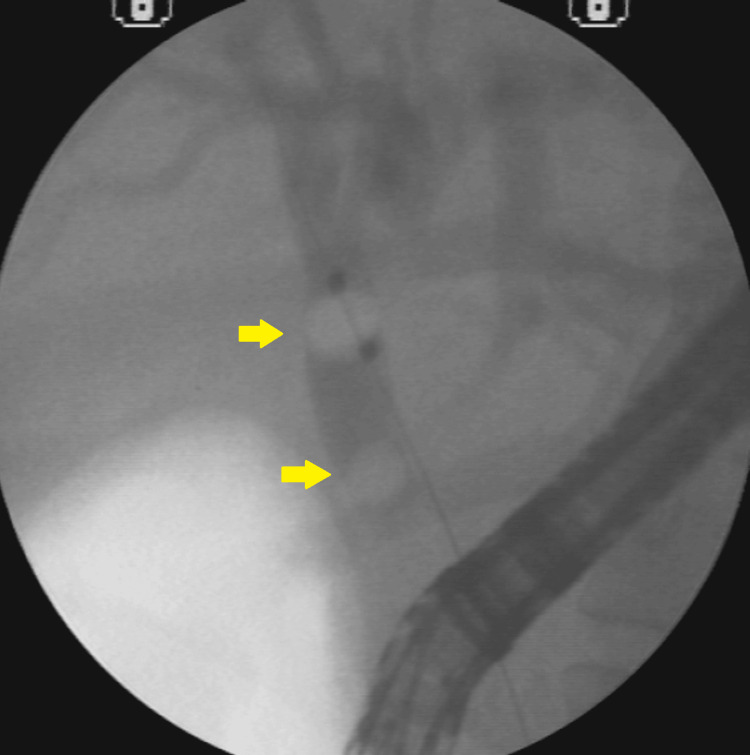

A 34-year-old white female patient with a body mass index (BMI) of 35 presented with right upper quadrant abdominal pain and jaundice, without fever. Imaging studies revealed cholelithiasis and choledocholithiasis. During ERCP, a small papilla of Vater was identified, making cannulation of the common bile duct (CBD) difficult; the guidewire repeatedly entered only the main pancreatic duct. The double-wire cannulation technique was therefore employed, allowing successful access to the bile duct (Figures 1–2).

Imaging revealed 10-mm calculi in the dilated proximal CBD and a long narrowing of the distal CBD (Figure 3).